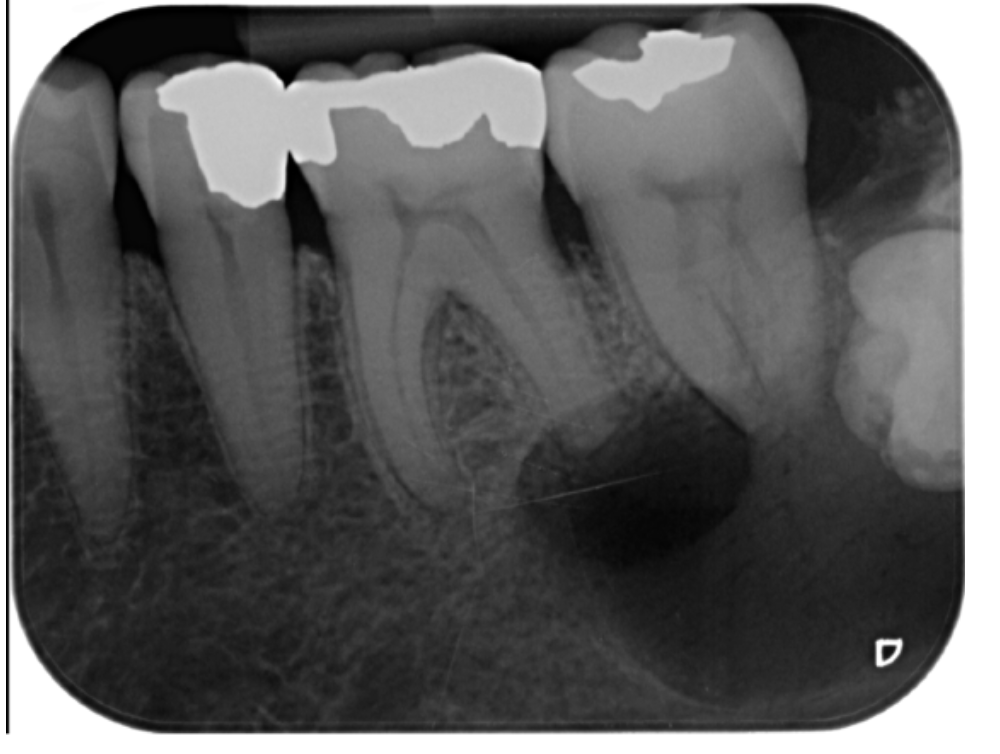

Examen radiographique

- Début : image radioclaire faible en « croissant de lune » au tiers apical

- Extension : image arrondie ou ovalaire, contours diffus, centre radioclaire, effacement de la trabéculation osseuse

- Persistance : destruction radiculaire (aspect « sucé »), destruction centrifuge de l’os alvéolaire

Piège diagnostique : Éviter la confusion avec des structures anatomiques normales : trou mentonnier, fossette incisive, canaux accessoires.

- Kyste péri-apical ou latéral : image > 10 mm, contours nets, fond homogène

- Ostéite raréfiante : image > 5 mm, contours flous

- Image radioclaire < 5 mm, contours diffus

- Radiographie : élargissement desmodontal, image radioclaire de 1 cm, contours arrondis nets

- Radiographie : image radioclaire homogène appendue à l’apex, bien délimitée

- Radiographie : géode radioclaire bien délimitée > 1 cm, liseré osseux dense, fond homogène

- Cathétérisation du trajet fistulaire avec un cône de gutta-percha pour identifier la dent causale (technique indispensable)

- Zone de raréfaction osseuse diffuse radioclaire

- Radiographie : élargissement desmodontal, zone de raréfaction osseuse

Problématique identifiée : La radiographie révèle une image radioclaire péri-apicale arrondie de 4 mm environ, à contours diffus, en regard des apex de la 36. Diagnostic retenu : granulome péri-apical (image < 5 mm, contours diffus, dent non vitale).